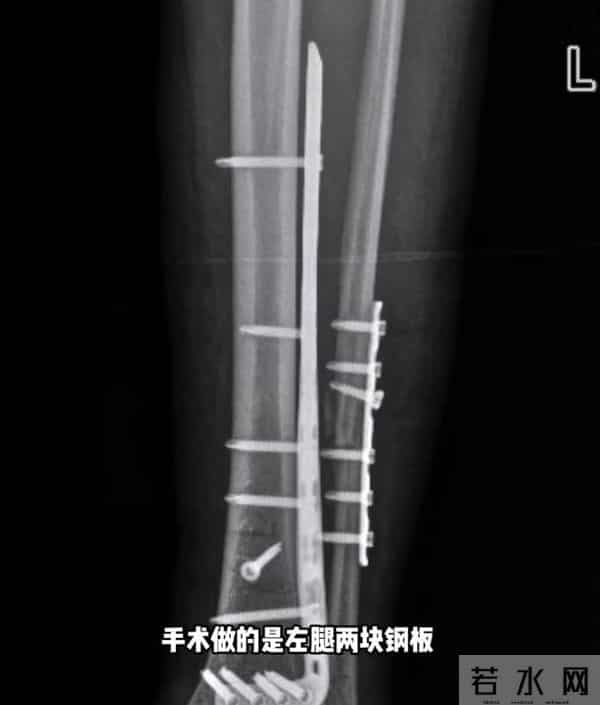

据她2月27日发布的动态,她在新疆滑雪时摔倒,断了4根骨头,右腿胫骨粉碎性骨折,处理伤口的时候,她痛苦喊叫声响彻诊室。

千一称在新疆接受手术,左腿2块钢板16颗钉子,右腿2条髓内钉和6颗固定钉子,缝了45针。